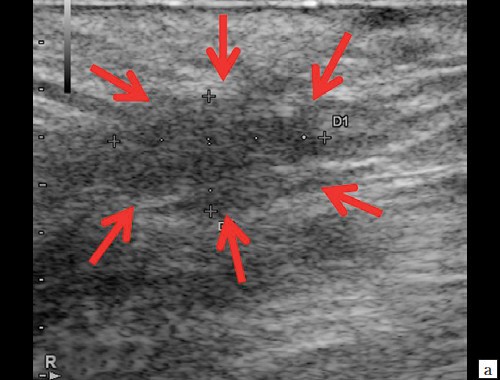

г – В-режим. По периферии образования ближе к ягодичной области – формирующийся свищевой ход размером 1,3×0,6×0,6 см (стрелки).

г – В-режим. Через 3 дня после оперативного вмешательства. Описываемый свищевой ход уменьшился в размере до 1,1×0,2×0,5 см (стрелки).

г, д – В-режим. Через 14 дней после оперативного вмешательства. Свищевой ход визуализируется нечетко, уменьшился в размере до 0,8×0,2×0,4 см (стрелки).